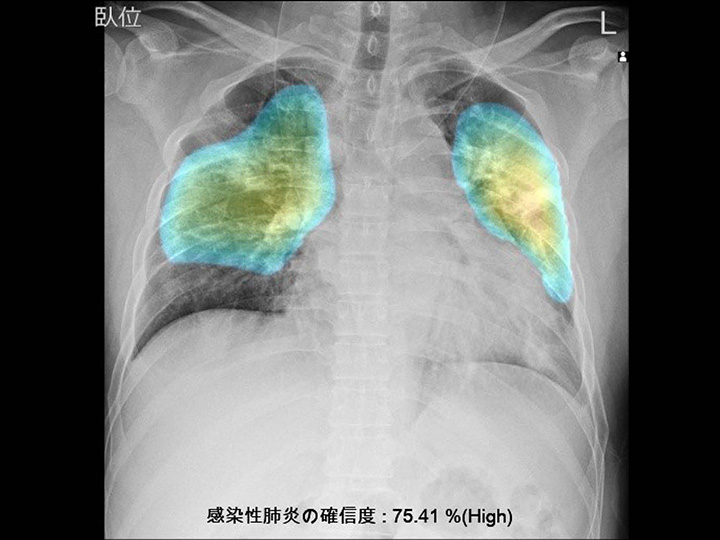

胸部CR×肺炎

DoctorNET JLK-CRP

胸部CR画像より、肺炎の確信度に応じたラベル・病変上のヒートマップを表示します

- 発熱外来での、肺炎の見落とし予防として